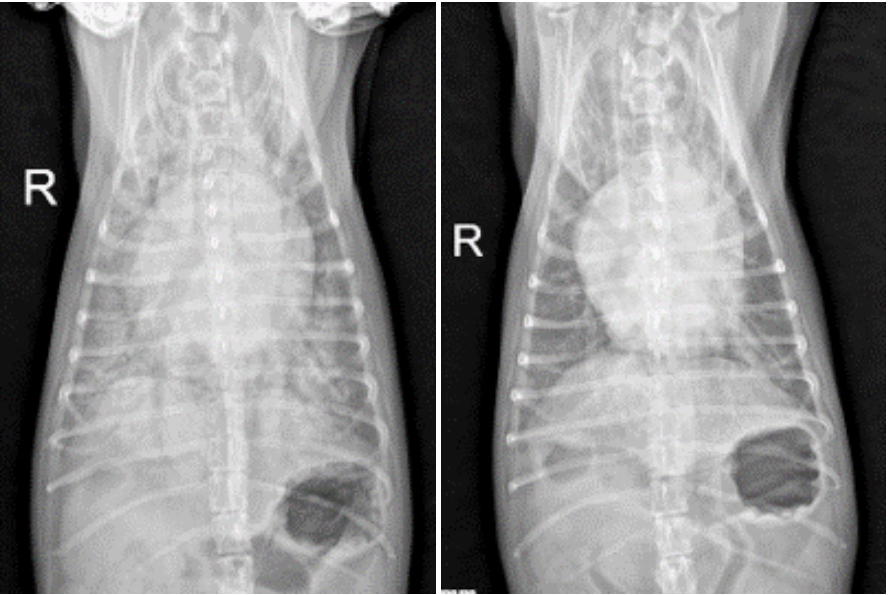

방사선 검사상 폐에 고여 있던 물(침윤)도 점차 흡수되며 개선되는 소견을 보였고, 이에 따라 승압제는 중단하였으며 이뇨제와 정맥확장제는 점차 감량하기 시작했습니다. ▼

내원 당시(좌), 입원 1일차 (우)

2. 입원 2일차

호흡과 혈압 상태가 계속해서 양호하게 유지되었고, 흉부 방사선 검사에서 심장과 좌심방의 크기, 폐 침윤이 의미 있게 감소한 것이 확인되었습니다. 이에 따라 이뇨제의 지속 정맥 주입(CRI)을 중단하고, 정맥 주사로 감량하여 유지 치료를 진행하였습니다. ▼